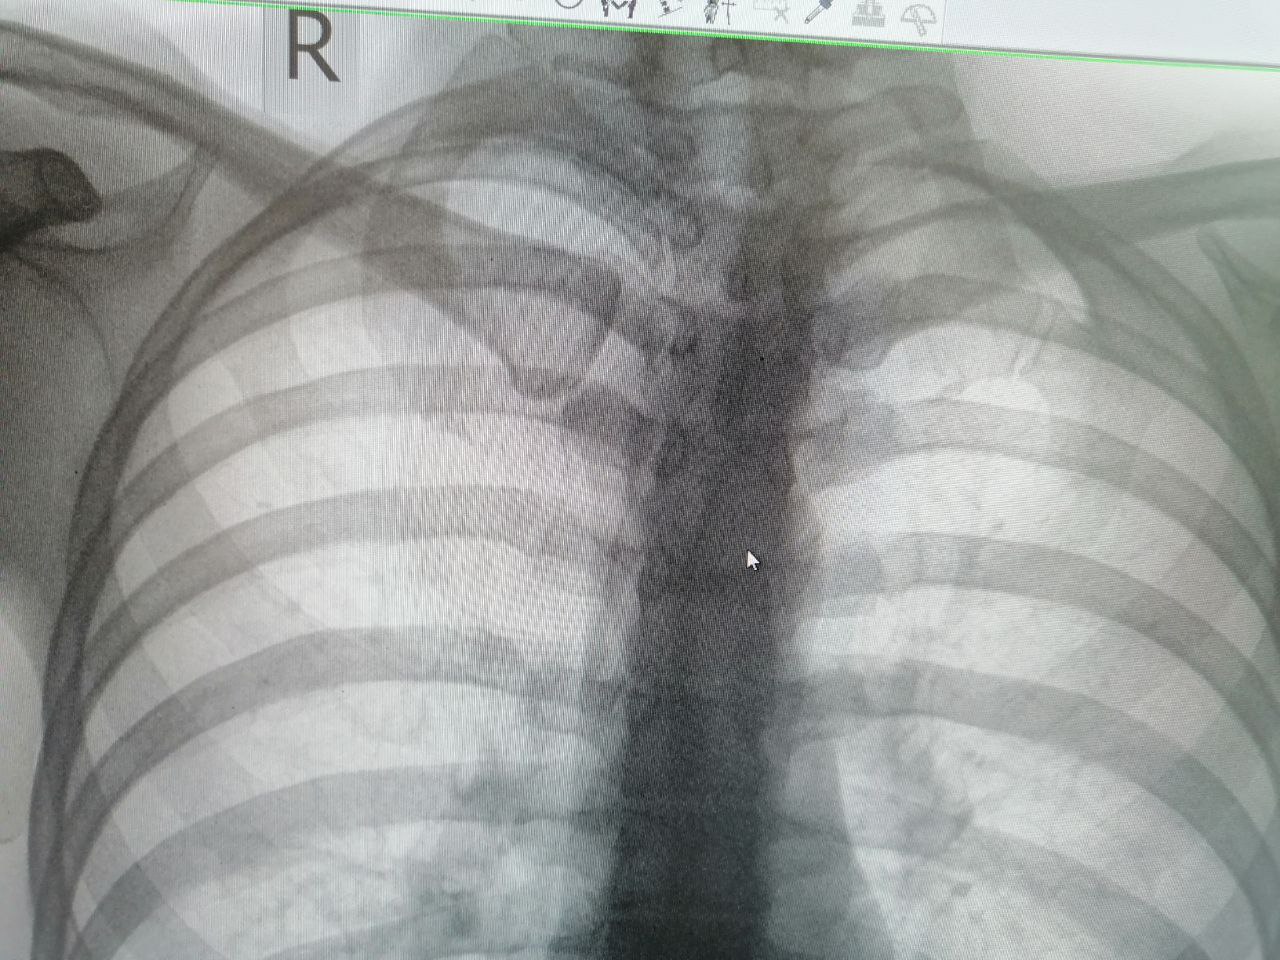

D

Dr.Tanechka in Radiology/Рентгенология Чат

Добрый день. Как правильно называется эта аномалия ребра?

Синостоз.